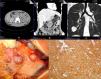

La tríada de Carney (tumor estromal gastrointestinal [GIST, por sus siglas en inglés], condroma pulmonar y paraganglioma extra-adrenal) es un síndrome multi tumor no hereditario muy raro que se caracteriza por predominancia femenina (85%) e inicio temprano de síntomas. Cuando no hay paragangliomas presentes, se le llama «tríada de Carney incompleta». Una mujer de 23años presentó una historia de 3meses de dolor epigástrico y pérdida de peso de 6kg. Su historia incluía gastrectomía distal por tumor de antro gástrico (leiomioma) 6años antes. Se estableció un diagnóstico positivo por medio de endoscopia gastrointestinal superior y tomografía computarizada (TC) abdominal con contraste, en las que se observaron 5tumores exofíticos de 1.0 a 6.0cm en la parte distal del estómago (fig. 1A,B). Una TC torácica mostró una masa calcificada (3.0cm de diámetro) en el lóbulo derecho inferior (S9) consistente con un condroma pulmonar benigno (fig. 1C). El diagnóstico presuntivo fue síndrome de tríada de Carney incompleto y la paciente fue sometida a gastrectomía subtotal (BillrothII) (fig. 1D). El reporte patológico fue consistente con un GIST de células mixtas con 4 mitosis por 50 campos de alto poder (HPFs, por sus siglas en inglés). La tinción inmunohistoquímica fue positiva para CD117/c-KIT (fig. 1E) y CD34. La paciente regresó a la clínica 2años después para someterse a remoción de condroma pulmonar sintomático. Posterior al seguimiento de 10años, la paciente no presenta síntomas ni progresión de la enfermedad o metástasis.

Vista axial (A) y vista coronal (B) de la TC abdominal con contraste donde se observan tumores multifocales en la parte distal del estómago. C)La TC torácica muestra una masa bien delimitada compatible con condroma pulmonar. D)Múltiples tumores nodulares en el antro gástrico. E)Células tumorales positivas para anticuerpo anti-CD117 (×100).